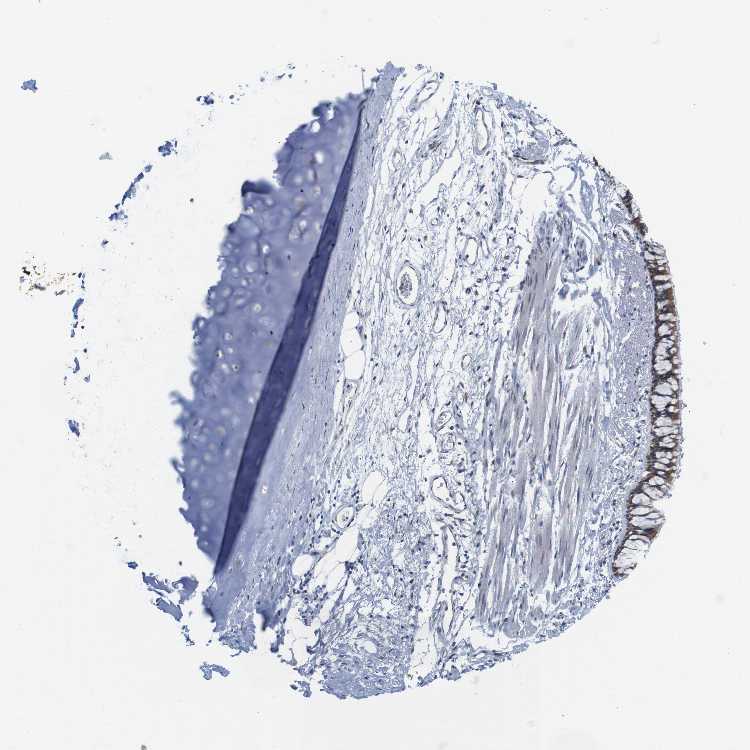

ADIPOSE TISSUE - Antibody stainingi

Antibody staining in the annotated cell types in the current human tissue is reported as not detected, low, medium, or high, based on conventional immunohistochemistry profiling in selected tissues. This score is based on the combination of the staining intensity and fraction of stained cells.

Each image is clickable and will lead to virtual microscopy that enables deeper exploration of all samples and also displays staining intensity scores, fraction scores and subcellular localization as well as patient and tissue information for each sample.

Antibody HPA014837

Adipocytes Not detected